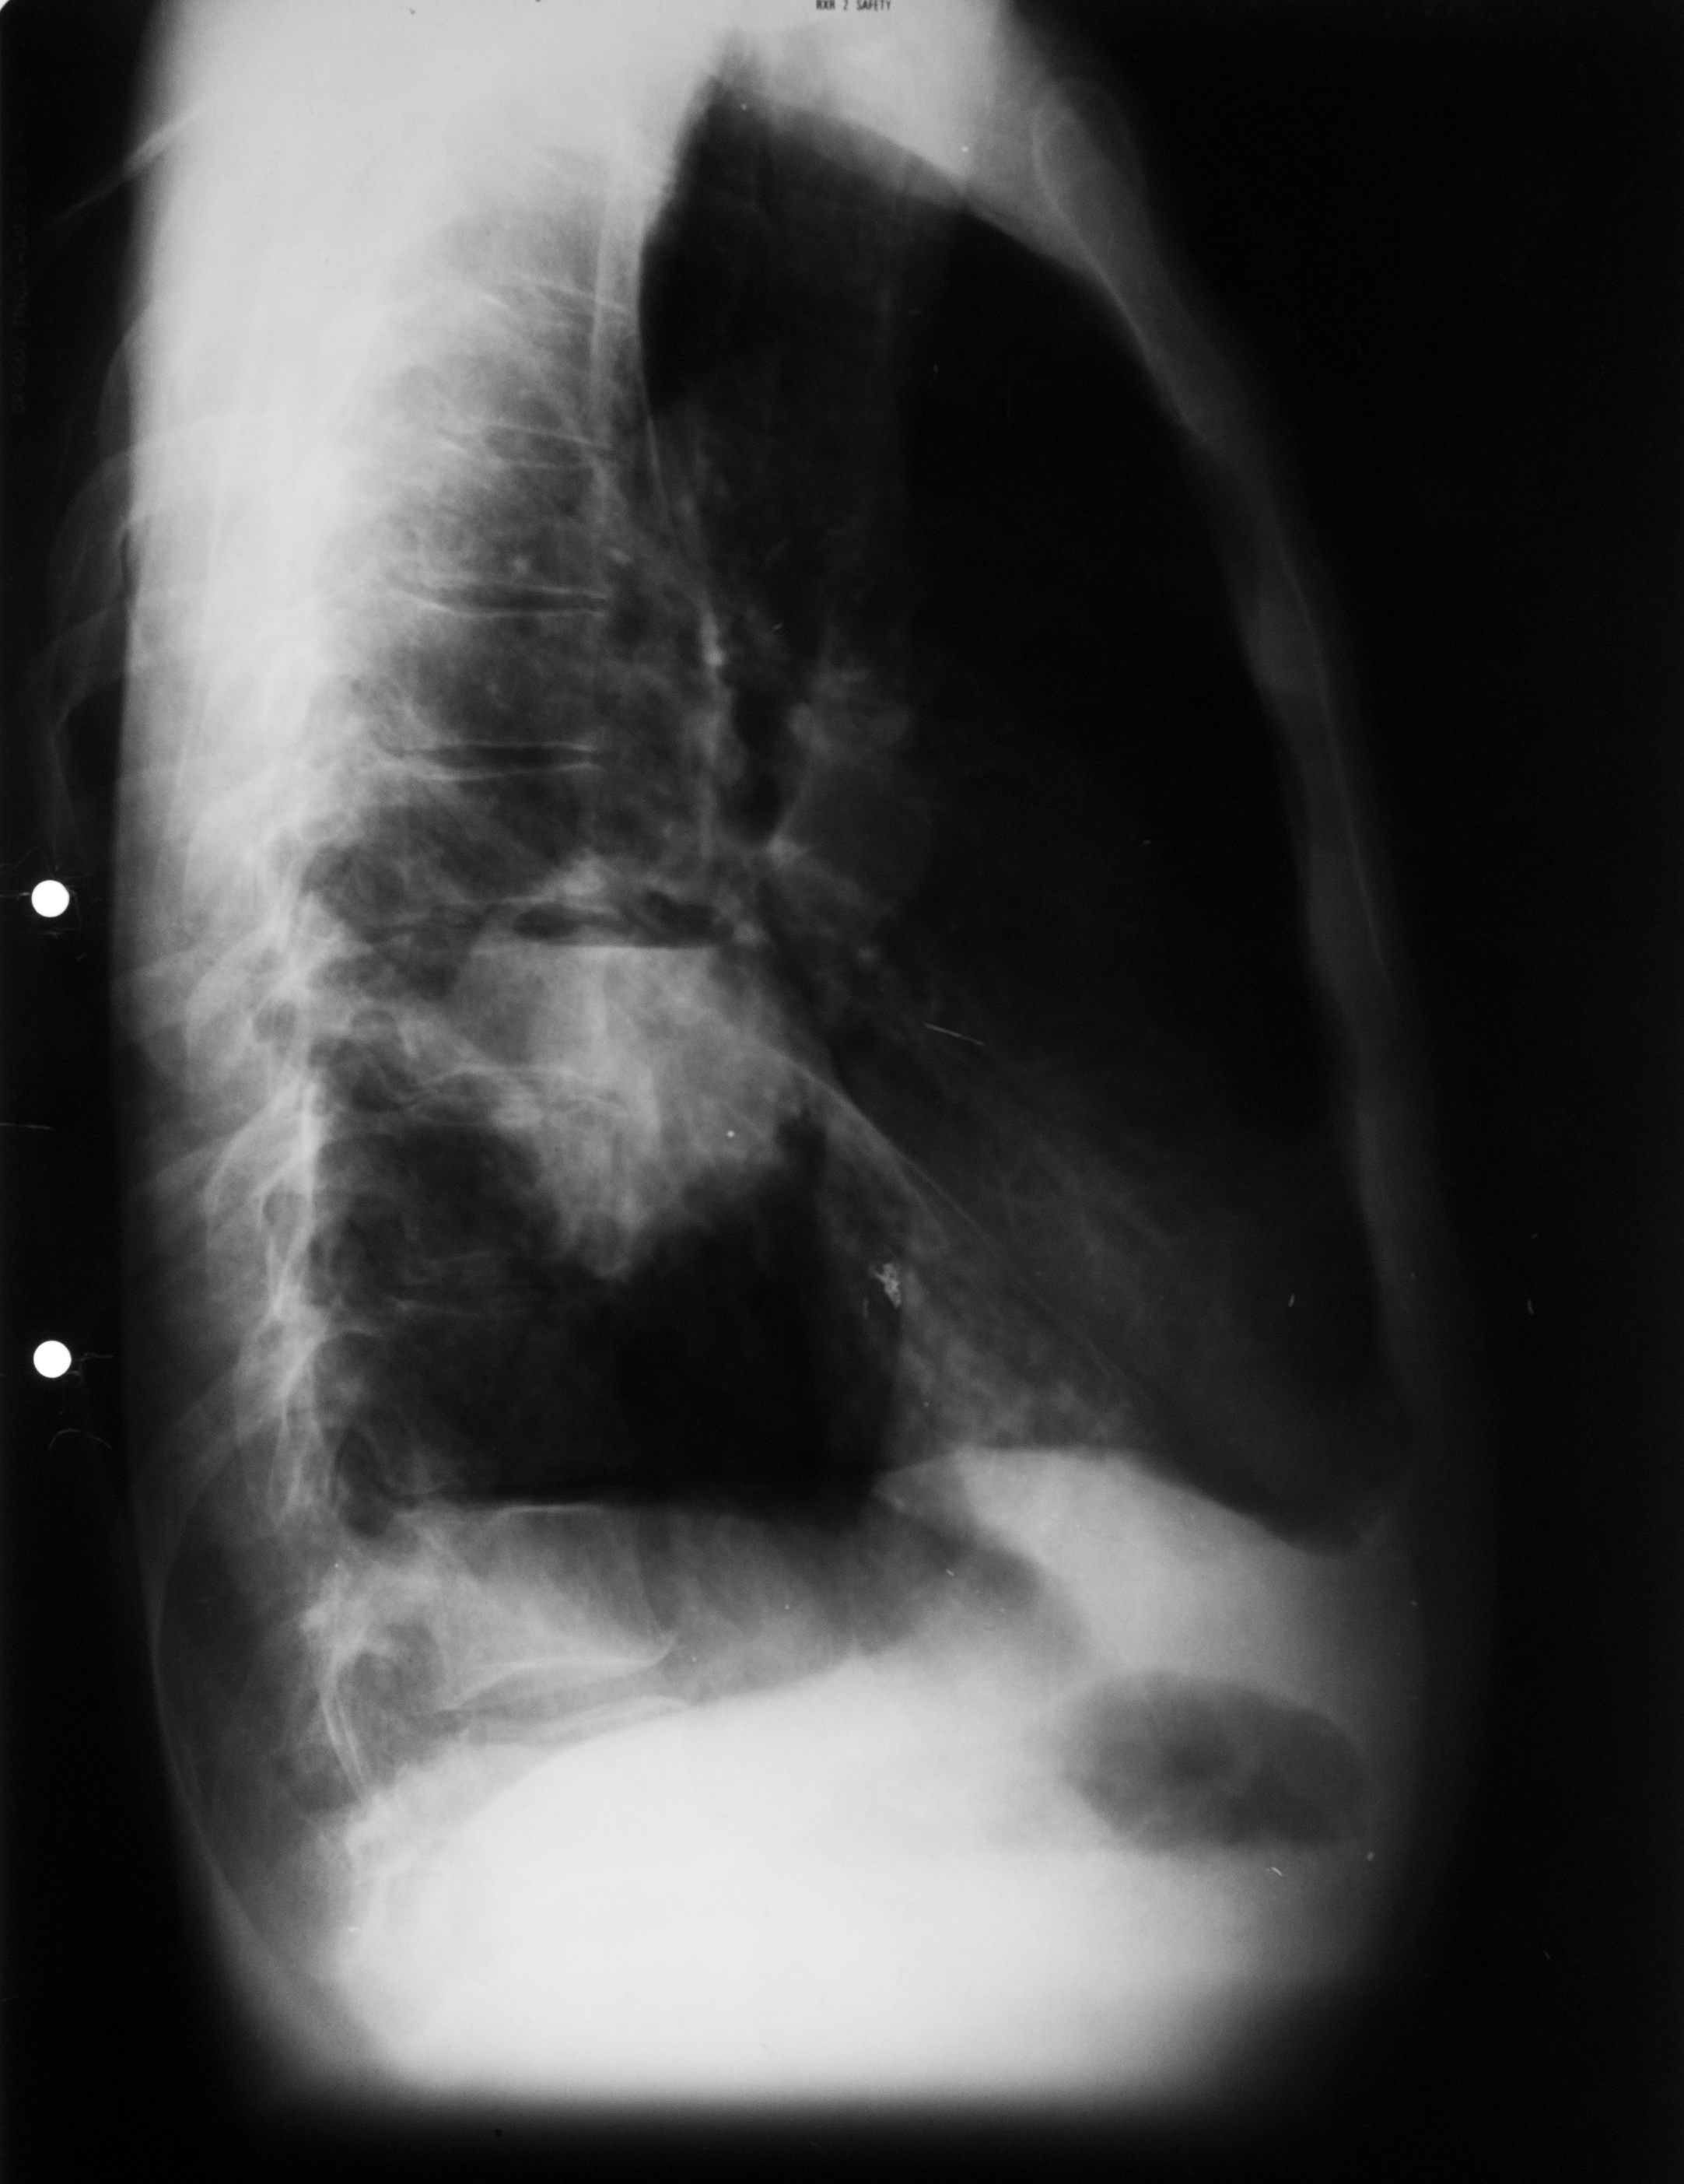

CHIST SUPRAINFECTAT VĂZUT DIN PROFIL (radiografie de profil)

Imagine hidroaerică,mixtă